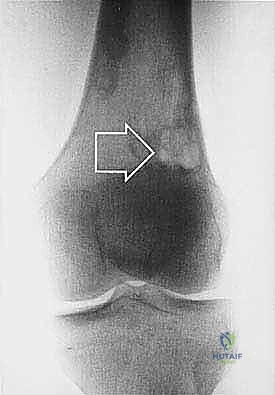

* الساركوما العظمية (Osteosarcoma): الأكثر شيوعاً، تظهر عادة حول الركبة (أسفل الفخذ أو أعلى القصبة).

| حدود الورم في الأشعة | واضحة، محددة بدقة (Sclerotic margin) | غير واضحة، متآكلة (Moth-eaten appearance) |

| اختراق قشرة العظم | نادر جداً | شائع جداً، يمتد للأنسجة الرخوة المحيطة |

تحديد مراحل الورم (Staging): نظام Enneking

تحديد مرحلة الورم هو الخطوة الأهم قبل أي تدخل جراحي. يعتمد الدكتور هطيف على نظام (Enneking) لتحديد مراحل أورام العظام، والذي يعتمد على ثلاثة عوامل:

2. الموقع (Site - T): هل الورم داخل الحيز العظمي (Intracompartmental - T1) أم اخترق القشرة وخرج للحيز الخارجي (Extracompartmental - T2)؟